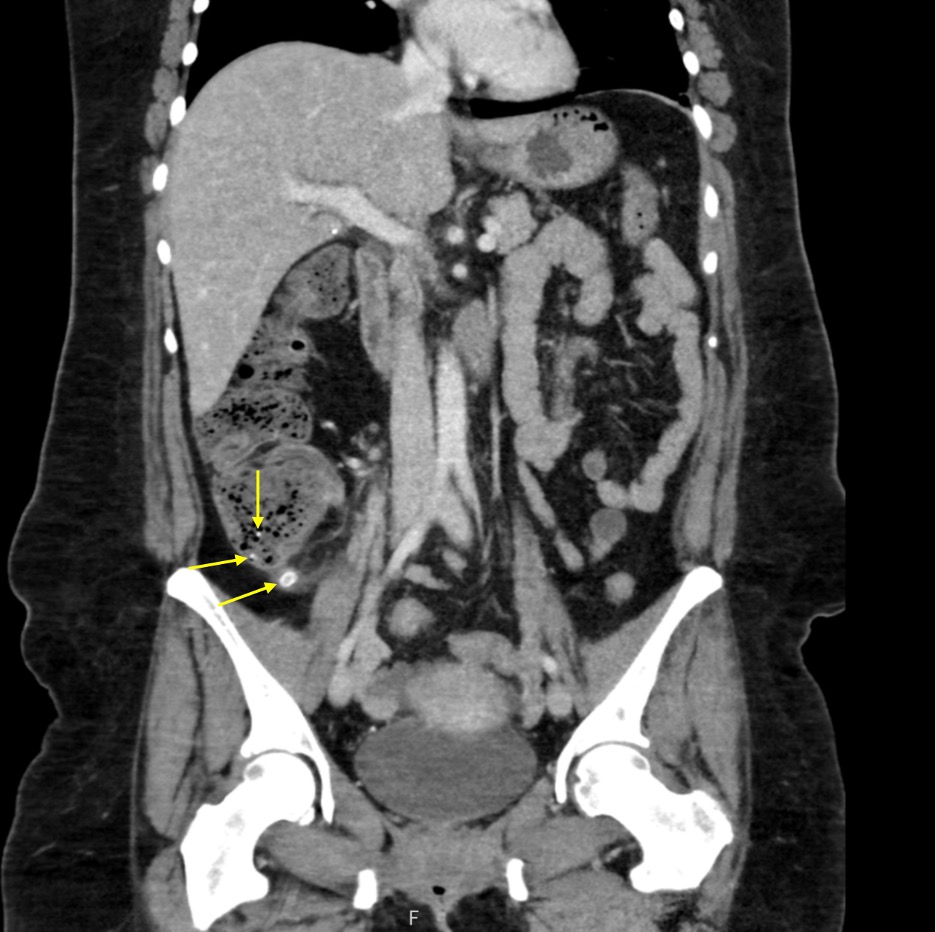

This case report highlights the clinical complexities of diagnosing and managing appendicitis complicated by appendicoliths in a 44-year-old female patient. Appendicitis is a common cause of acute abdominal pain, with imaging playing a crucial role in diagnosis. The patient presented with symptoms of right lower quadrant pain, nausea, vomiting, and chills that were initially misattributed to menstrual cramps. Diagnostic evaluation revealed multiple appendicoliths via computed tomography (CT), and the decision for laparoscopic appendectomy was based on the imaging results and clinical presentation. Intraoperative findings showed gangrenous but non-perforated appendicitis. The patient’s postoperative recovery was uneventful, with successful symptom resolution. This case highlights the importance of considering appendicitis in the differential diagnoses for acute abdominal pain in females, particularly with overlapping gynecological symptoms. The high sensitivity of CT imaging for appendicitis and the necessity of timely surgical intervention in cases involving appendicoliths are discussed. Multimodal imaging and prompt surgical management are vital for favorable outcomes in complicated appendicitis cases.